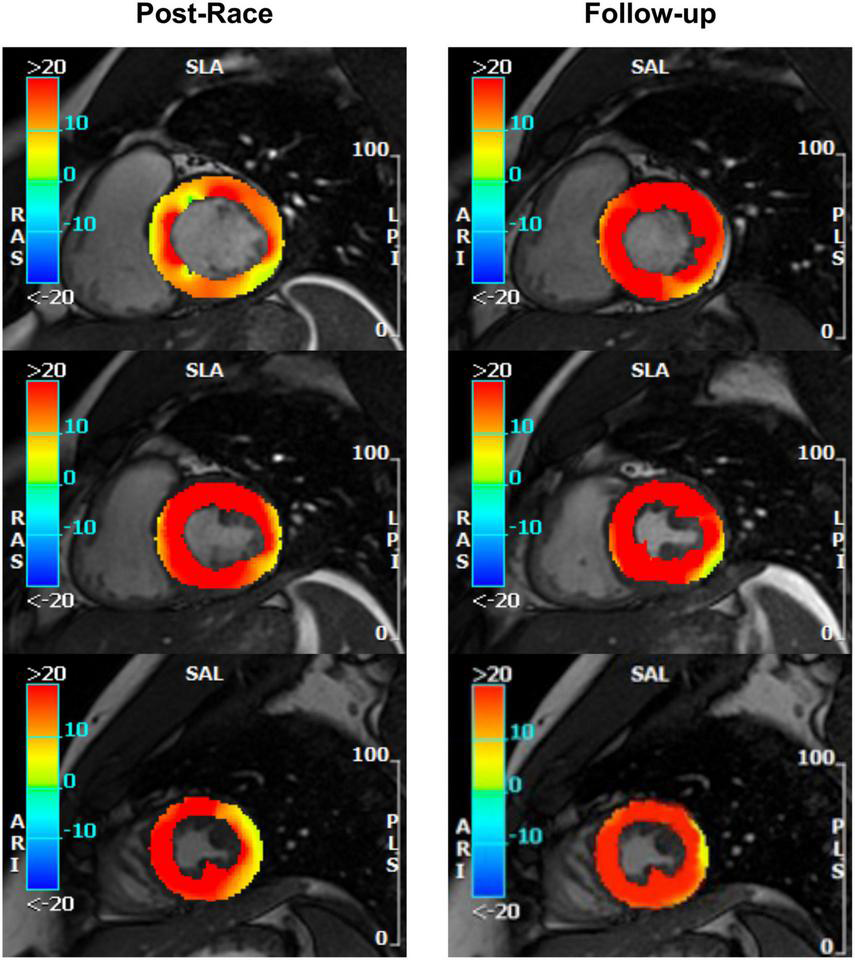

Immediate postrace and follow-up assessment of global, basal, middle, and apical LV myocardial edema are shown in Table 4. Compared with follow-up, the extent of myocardial edema was significantly higher immediately after the competition (postrace: 10.5 ± 6% LV mass vs. follow-up: 3.9 ± 3.8% LV mass, P = 0.004; Figure 4) and presented with a relative apical sparing distribution (P < 0.001) and a basal-to-apical gradient (Figures 5, 6). There was a significant inverse relationship between temporal changes in radial strain and myocardial edema, both tracking the basal-to-apical distribution of edema, or edema localized at basal LV segments (Figures 7, 8). In one case, increased T2-STIR signal intensity remained unchanged in midsegments and increased in the apical segments at follow-up assessment; however, the presence of breathing artifacts located at mid and apical levels is the most likely explanation for this isolated finding. No LGE was detected immediately postrace or during follow-up CMR for any of the triathletes.

FIGURE 6

www.frontiersin.org

Figure 6. Myocardial edema: Postrace vs. 30-day follow-up. Example of postrace and 30-day follow-up resting T2-STIR images (basal, middle, and apical slices from the complete dataset of short-axis views). Edema was evaluated semi-quantitatively as signal intensity (SI) greater than mean + 2 SD. As shown in the left panels, edema was detected in the postrace acquisition and not at rest (right panels). Moreover, a basal-to-apex gradient was found as the SI ratio basal/apex was greater in postrace than at 30-day follow-up.